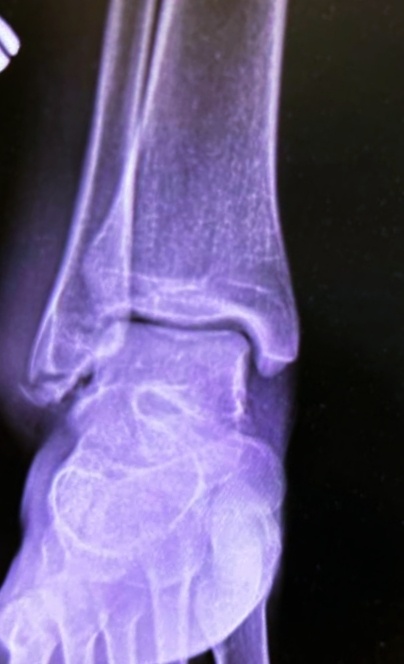

Мужчина , 34 года, на снимок голеностопа.

–Да я просто был у вас в больнице, недели три назад, с этой же проблемой, мне поставили растяжение, и отпустили домой, дома я мазал всем, что прописали, носил ортез, но так сильно стало в пятку отдавать, что не выдержал боли, жена сказала , в платную идти.Я сходил, а там мне сказали, что перелом есть.

Так-то видно, что что-то есть, да?То ли свежий, то ли нет, но пациент говорит , что больше не травмировал конечность.

Найдут ему его прошлые снимки и отдадут, и два варианта развития событий:или этот перелом действительно свежий или судебный иск.

–Вот, если проглядели перелом,-говорит Боря, –то сейчас нехилую компенсацию высудит.

–Ну, такой перелом как могли проглядеть? Он же очевидный!

–А, да бог его знает, как, но есть подозрение, что ему и стопу могли назначить, да и снять чисто стопу, вот и проглядели, если сначала кости не сместились сильно.

–Да ты что! Он же сказал, что растяжение голеностопа поставили.

–Ну, или , к примеру, ночью встал и подвернул повторно и не помнит.